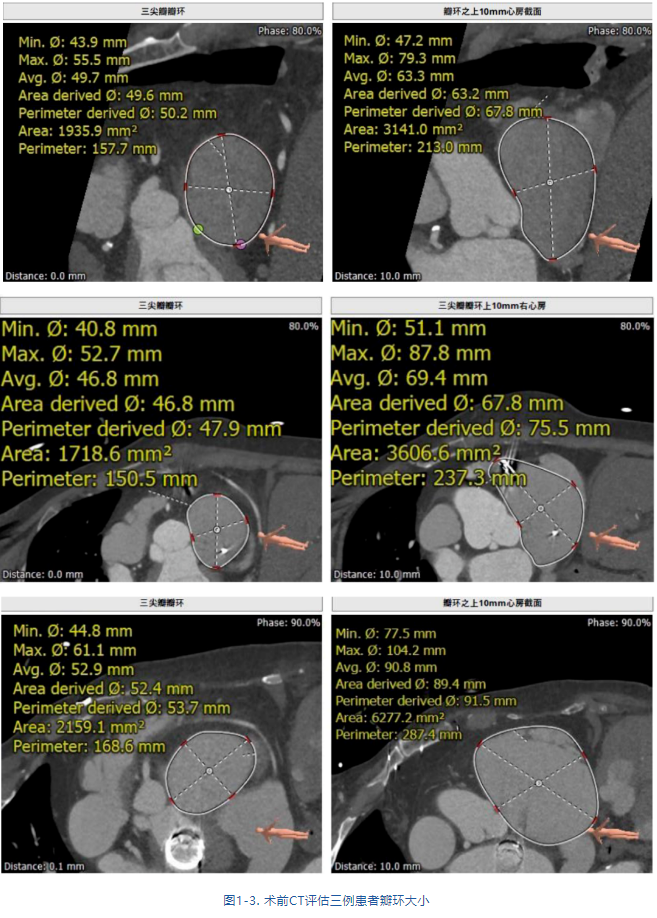

接受治療的是三例重度三尖瓣反流患者,術前基礎疾病多,均患有嚴重心律失常,其中兩例患者NYHA心功能Ⅱ/Ⅲ級。結合術前CT評估結果,三例患者的自體瓣環都較大(圖1-3),最大者平均瓣環為53.7mm;有一例患者有起搏器植入史,術中操作有纏繞起搏器導線的風險;三例患者入路血管均無嚴重迂曲和鈣化。經術前討論分析,潘湘斌教授及其團隊潘家華教授、朱達教授、王首正教授以及心超室的駱志玲教授,董念國教授及其團隊謝明星教授、尚小珂教授、陳澍教授、鐘禹成教授經過討論決定,采用創新的 LuX-Valve Plus經血管三尖瓣置換系統對患者進行手術。LuX-Valve Plus是我國自主研發的經血管介入三尖瓣置換系統,經頸靜脈入路的微創方式可進一步降低對患者的創傷。